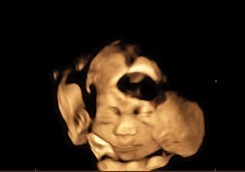

26+5w ลูกสาวค่ะ